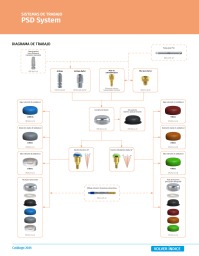

Protocolo